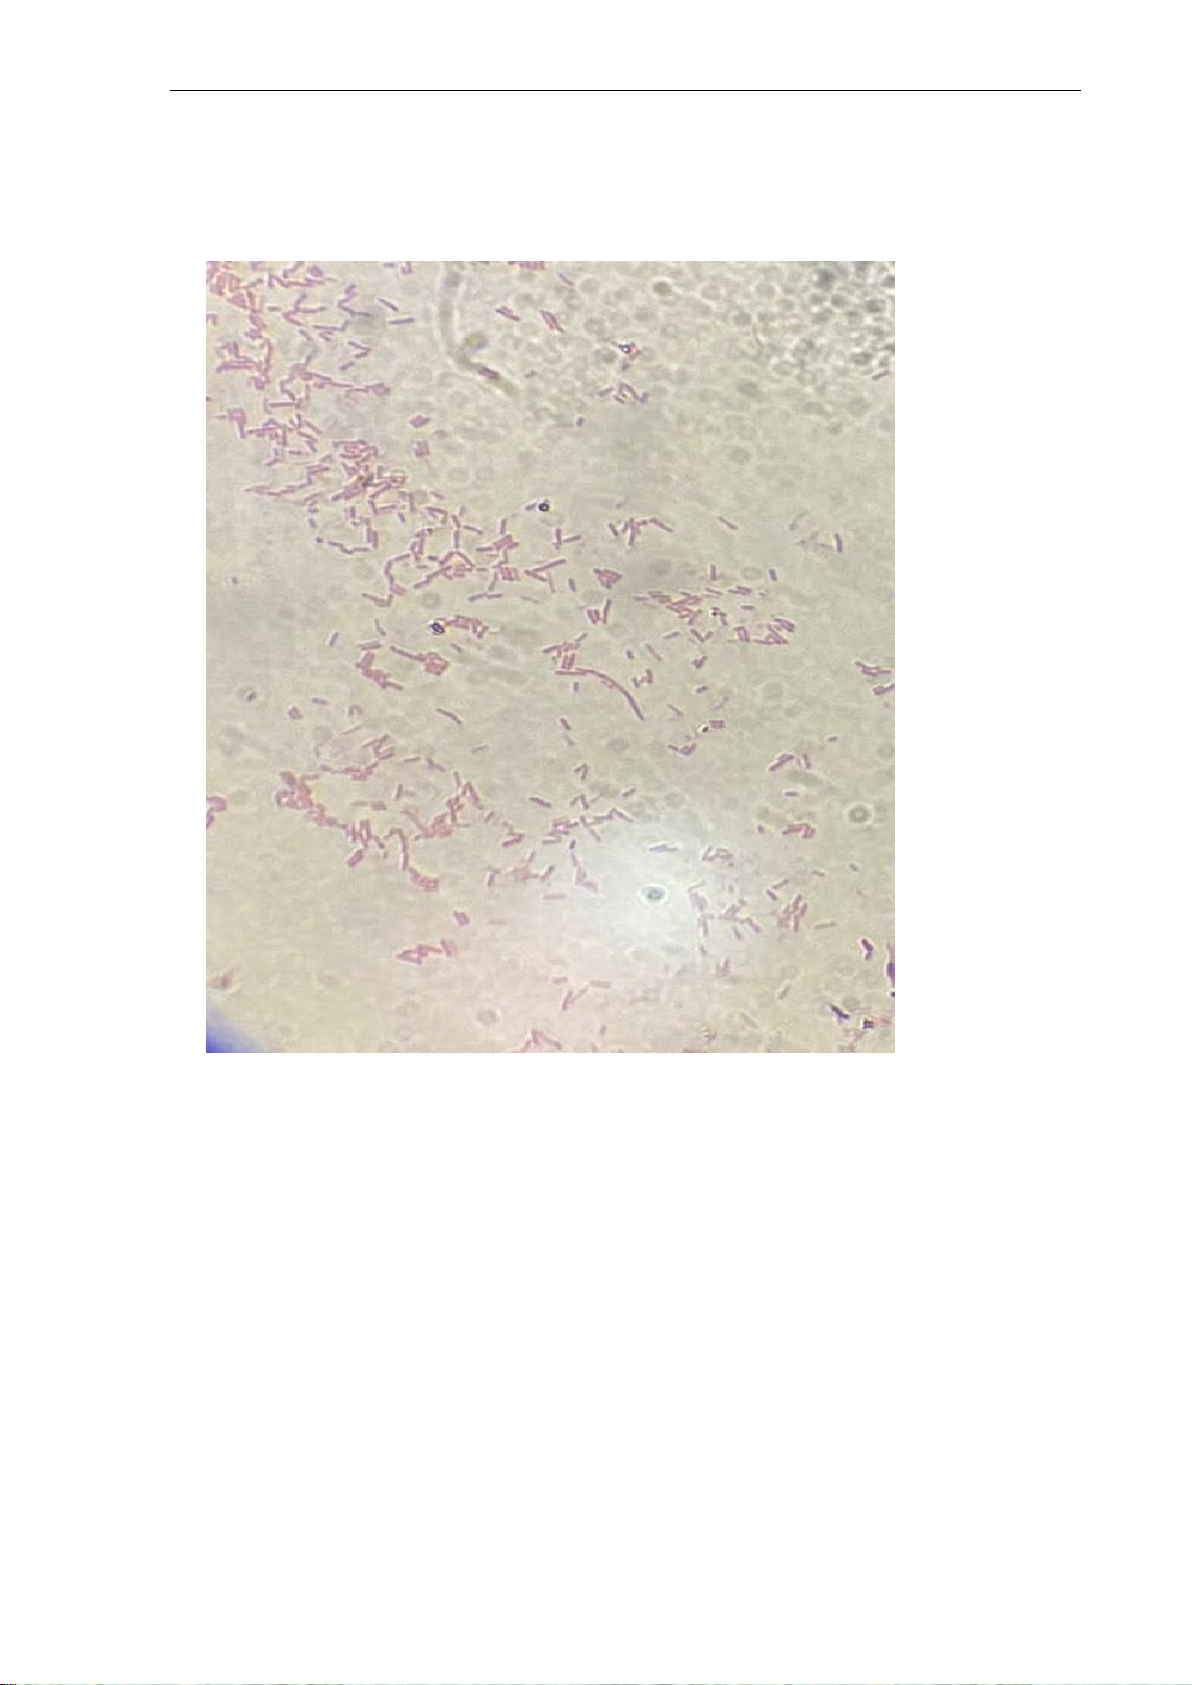

- Mô tả cách sắp xếp và hình dạng vi khuẩn trên lame kính của

mẫu nhuôm kháng aciḍ Màu sắc

Hình dạng vi khuẩn Cách sắp xếp Hồng Hình que

Rải rác, đơn lẻ hoặc nhóm nhỏ a.

Đọc kết quả của mẫu nhuôṃ

kháng acid

AFB/100 quang trường AFB/1 quang trường Kết quả (+++) (toàn bộ lam kính) b.

Chụp hình nhuôm ̣ kháng acid lOMoARcPSD| 60380256 lOMoARcPSD| 60380256